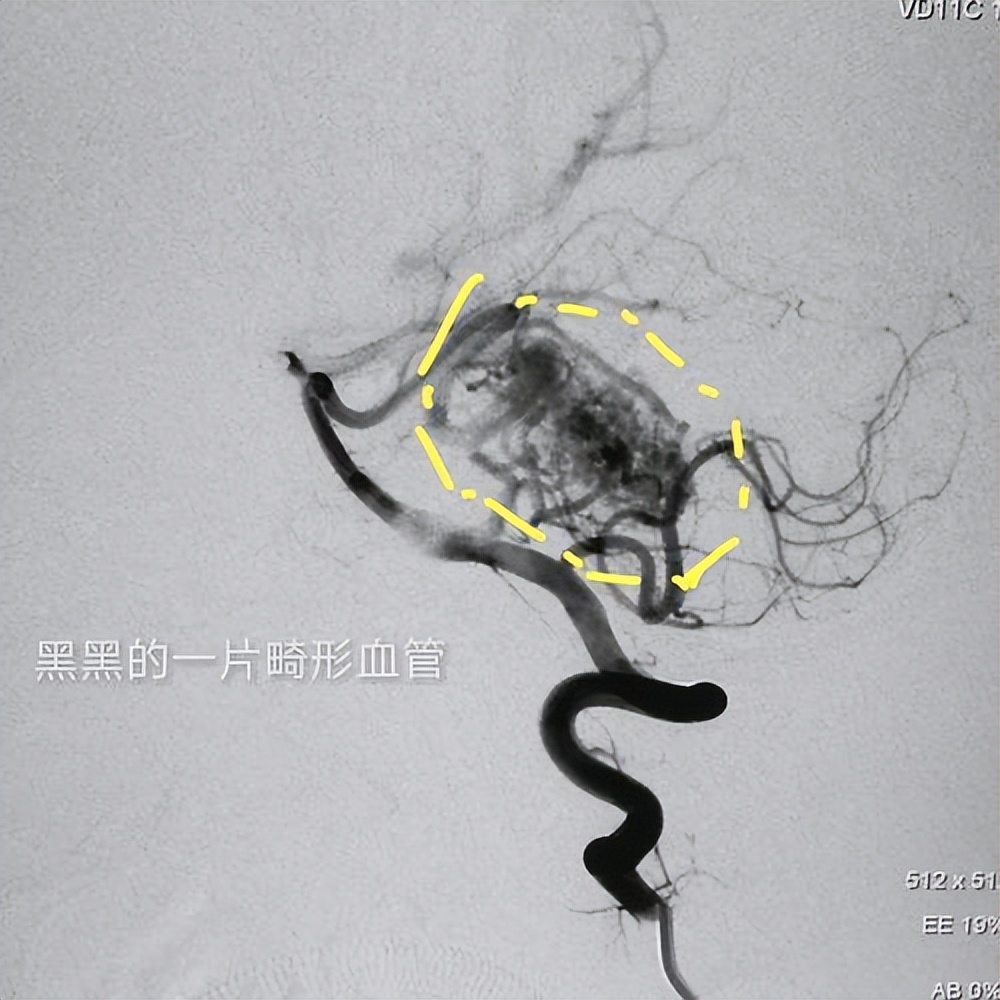

脑血管瘤是一种血管系统中的异常血管结构,它通常在大脑或脑膜中形成。脑血管瘤可以分为两种主要类型:动静脉畸形和血管母细胞瘤。

动静脉畸形是由动脉和静脉之间的异常血管连接组成的,导致了血液在这些畸形血管中流动不畅,这种类型的脑血管瘤通常是先天性的,但可能在生长过程中逐渐显现出来。

某些先天性血管畸形疾病,如脑动静脉畸形(AVM)或海绵状血管瘤,就有较大的概率导致脑血管瘤的发生,而且这种先天性的脑血管畸形发生破裂的概率较高,一定要预防好。